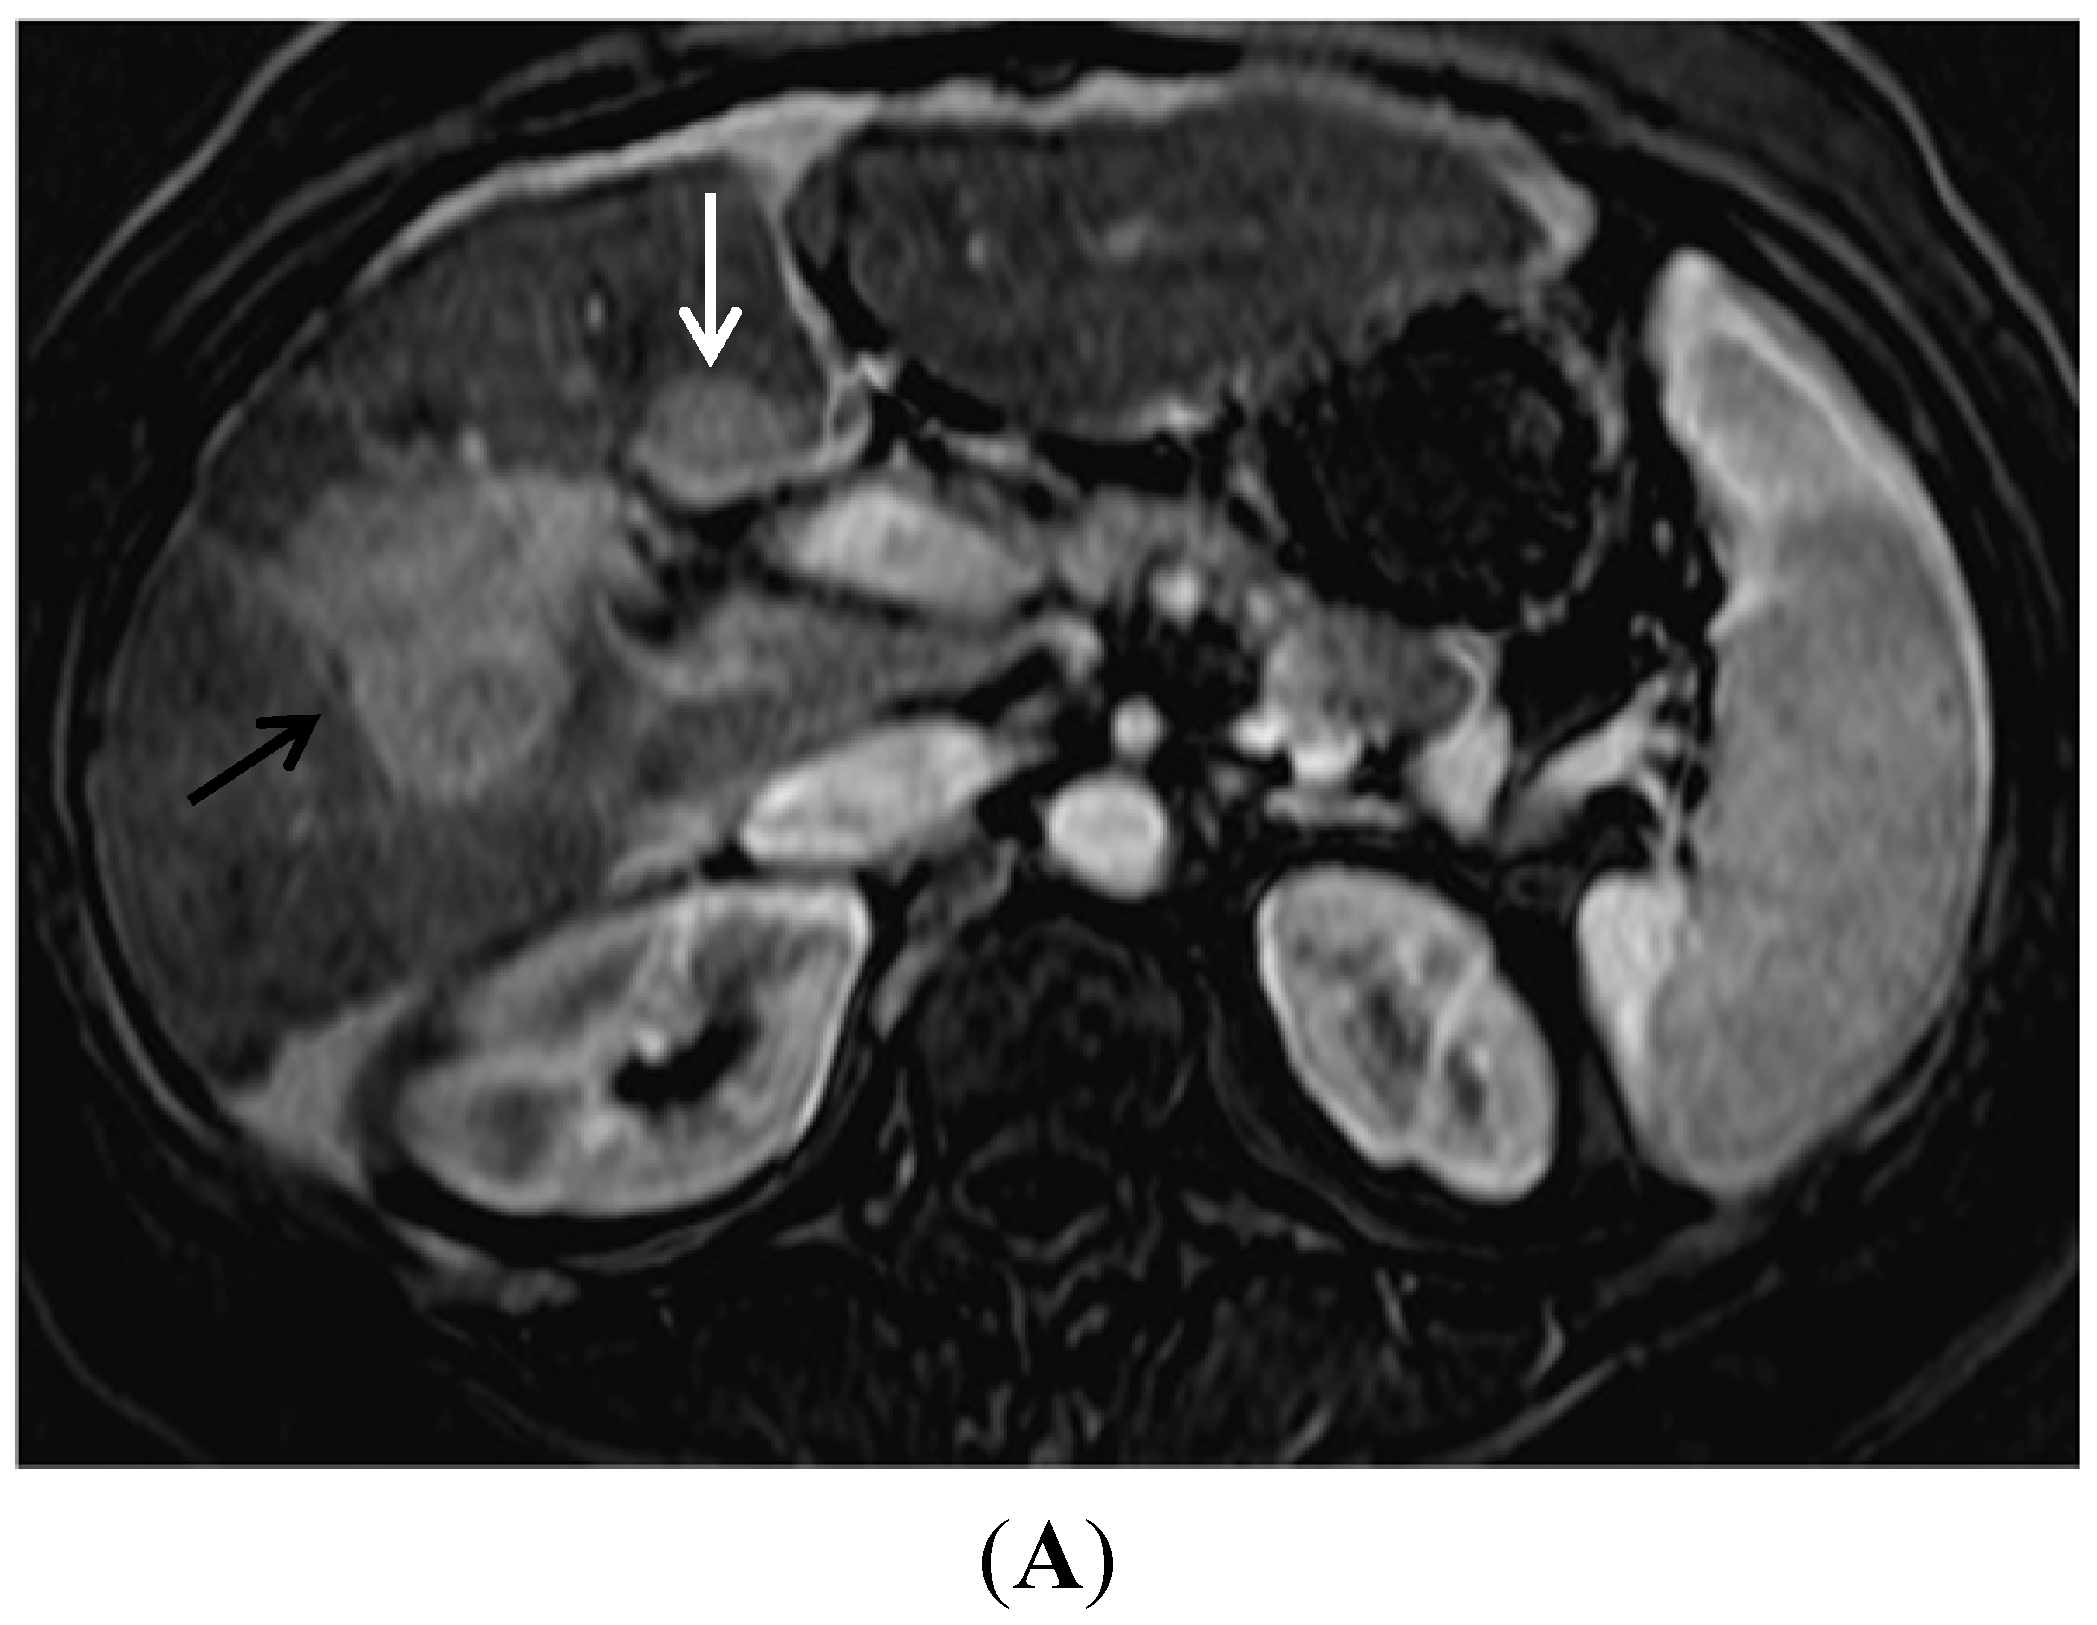

- Sandrasegaran, K.; Tahir, B.; Nutakki, K.; Akisik, F.M.; Bodanapally, U.; Tann, M.; Chalasani, N. Usefulness of conventional MRI sequences and diffusion-weighted imaging in differentiating malignant from benign portal vein thrombus in cirrhotic patients. Am. J. Roentgenol. 2013, 201, 1211–1219. [Google Scholar] [CrossRef] [PubMed]

- Shah, Z.K.; McKernan, M.G.; Hahn, P.F.; Sahani, D.V. Enhancing and expansile portal vein thrombosis: Value in the diagnosis of hepatocellular carcinoma in patients with multiple hepatic lesions. Am. J. Roentgenol. 2007, 188, 1320–1323. [Google Scholar] [CrossRef] [PubMed]

- Choi, J.Y.; Lee, J.M.; Sirlin, C.B. CT and MR imaging diagnosis and staging of hepatocellular carcinoma: Part I. Development, growth, and spread: Key pathologic and imaging aspects. Radiology 2014, 272, 635–654. [Google Scholar] [CrossRef] [PubMed]